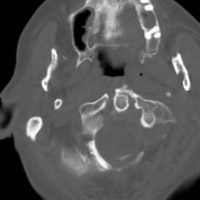

- Click on the image for a larger versionBAxial CT. This demonstrates the fracture of the anterior arch of C1.